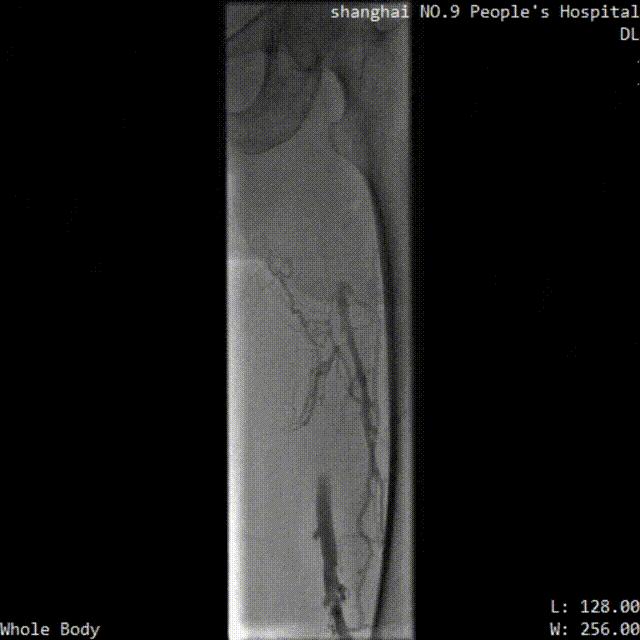

※ LuVoCaptor取栓前后管腔造影对照:

取栓术前管腔造影

取栓术后管腔造影

※ 手术过程:

患者仰卧位,穿刺膝右侧股总静脉,造影定位下腔静脉,肾静脉位置,穿刺腘静脉,放置可回收腔静脉滤器;穿刺左侧腘静脉,置入导鞘,使用LuVoCaptor取栓导管作用靶病变,实施取栓后,造影检查示血栓清除率>90%,取栓后靶血管残余狭窄50%。导丝导管配合通过左髂静脉狭窄闭塞段返回真腔,后行球囊扩张术,再植入Wallstent支架。再次造影见左股浅静脉、股静脉、髂静脉、腔静脉、滤器内连续显影,未见明显充盈缺损,管壁形态血流速度快,造影剂无外渗。支架植入后靶病变狭窄10%。